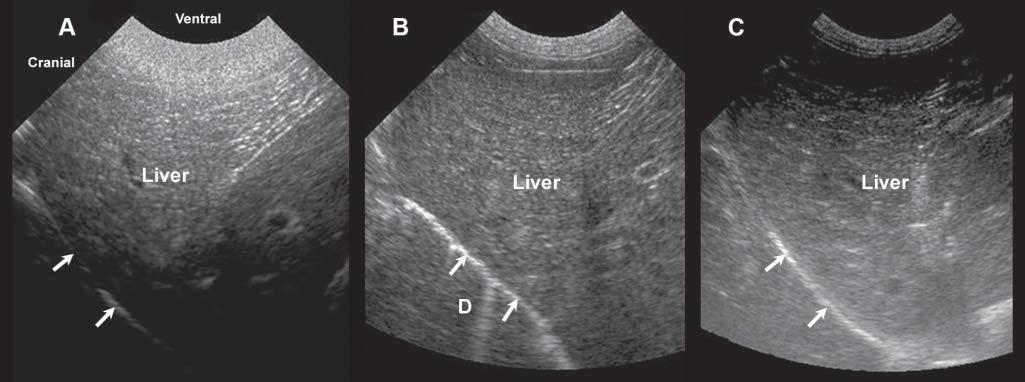

Figure1.8. Gainsetting. Becauseoftheattenuationoftheultrasoundbeamasittravelsthroughsofttissues,theamplification ofechoesreceivedmustbeadjustedaccordingtotissuetypeanddepth.Thismodulationcanbemadeusingtimegaincompensationbarsorfar/near/generalgainknobs.Thesethreeimagesshowthevariationinechogenicityofanormalliverwith excessiveneargainandinsufficientfargain (A),well-adjustednearandfargains (B),andinsufficientneargainandexcessive fargain (C). D,diaphragminterface.

The gain determinesthelevelofamplificationof echoestocompensatefortheirattenuationintissues, increasingthebrightnessofcorrespondingpixelson thescreen.Itcanbeadjustedgenerally,ormodulated specificallyindepth(Figure1.8).Timegaincompensation(TGC)isadjustedthroughslidingknobs, reducingsuperficialamplificationorincreasingdepth amplification,forinstance.Asultrasoundattenuation willvaryfromoneanimaltoanotherandfromone abdominalregiontoanother,dependingontheacousticcharacteristicsofnormalandabnormaltissues, boththegeneralgainandTGCwillhavetobeadjusted duringtheexamination.